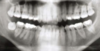

In this case, what 'other radiographic finding' would you note + mention to patient

Overhang on restoration of 7 - risk of fracturing during extraction of 8